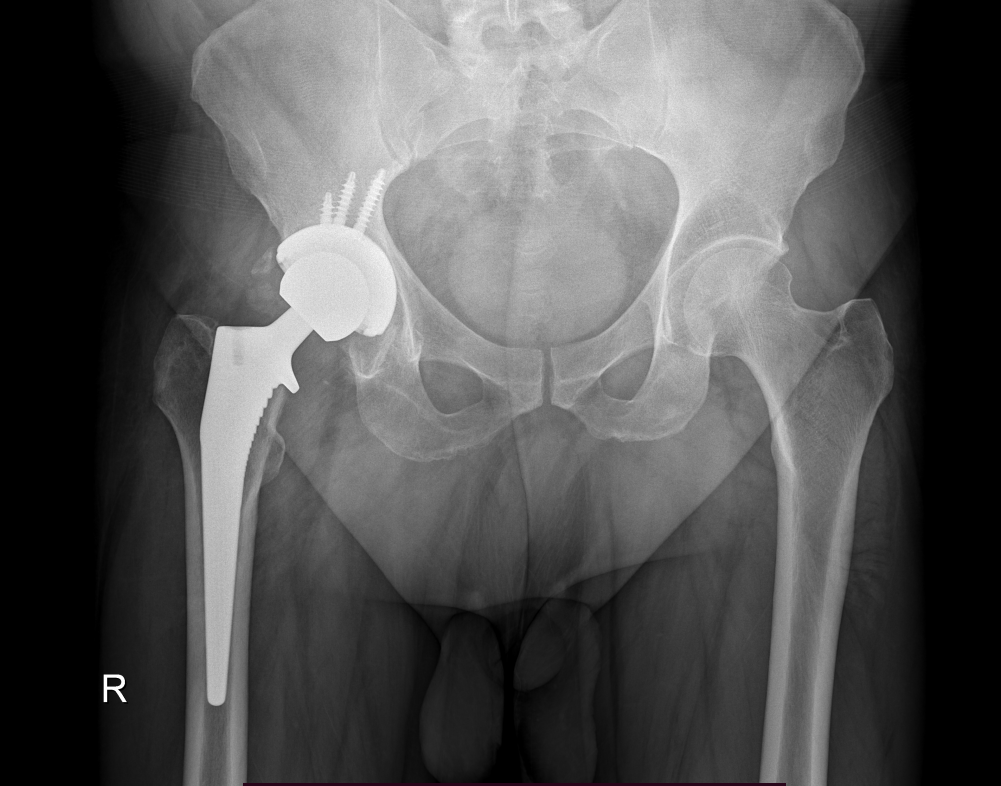

The surgery is performed under general anesthesia. During the procedure a surgical cut is made over the hip to expose the hip joint and the femur is dislocated from the acetabulum. The surface of the socket is cleaned and the damaged or arthritic bone is removed using a reamer. The acetabular component is inserted into the socket using screws or occasionally bone cement. A liner made of plastic, ceramic or metal is placed inside the acetabular component. The femur or thigh bone is then prepared by removing the arthritic bone using special instruments, to exactly fit the new metal femoral component. The femoral component is then inserted to the femur either by a press fit or using bone cement. Then the femoral head component made of metal or ceramic is placed on the femoral stem. All the new parts are secured in place using special cement. The muscles and tendons around the new joint are repaired and the incision is closed.

Surgical Procedure

Surgery may be recommended, if conservative treatment options such as anti-inflammatory medications and physical therapy do not relieve the symptoms.